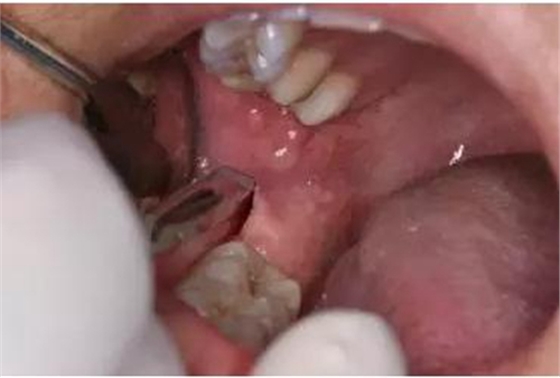

圖9.翻小瓣、用骨膜剝離器輕柔牽拉頰側(cè)齦瓣、暴露48合面

圖10.普通牙挺放置在48牙冠的近中根面與牙槽嵴頂之間,采用推力和挺力,挺松48.